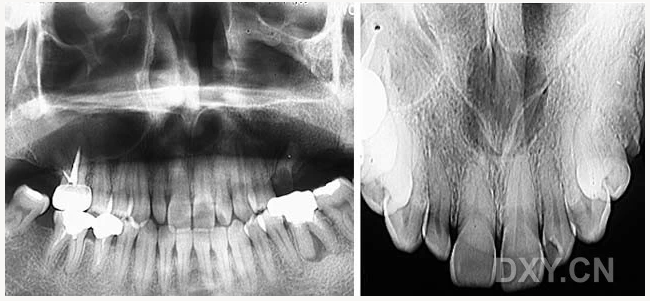

成釉細胞瘤

鼻鄂囊腫

根尖囊腫